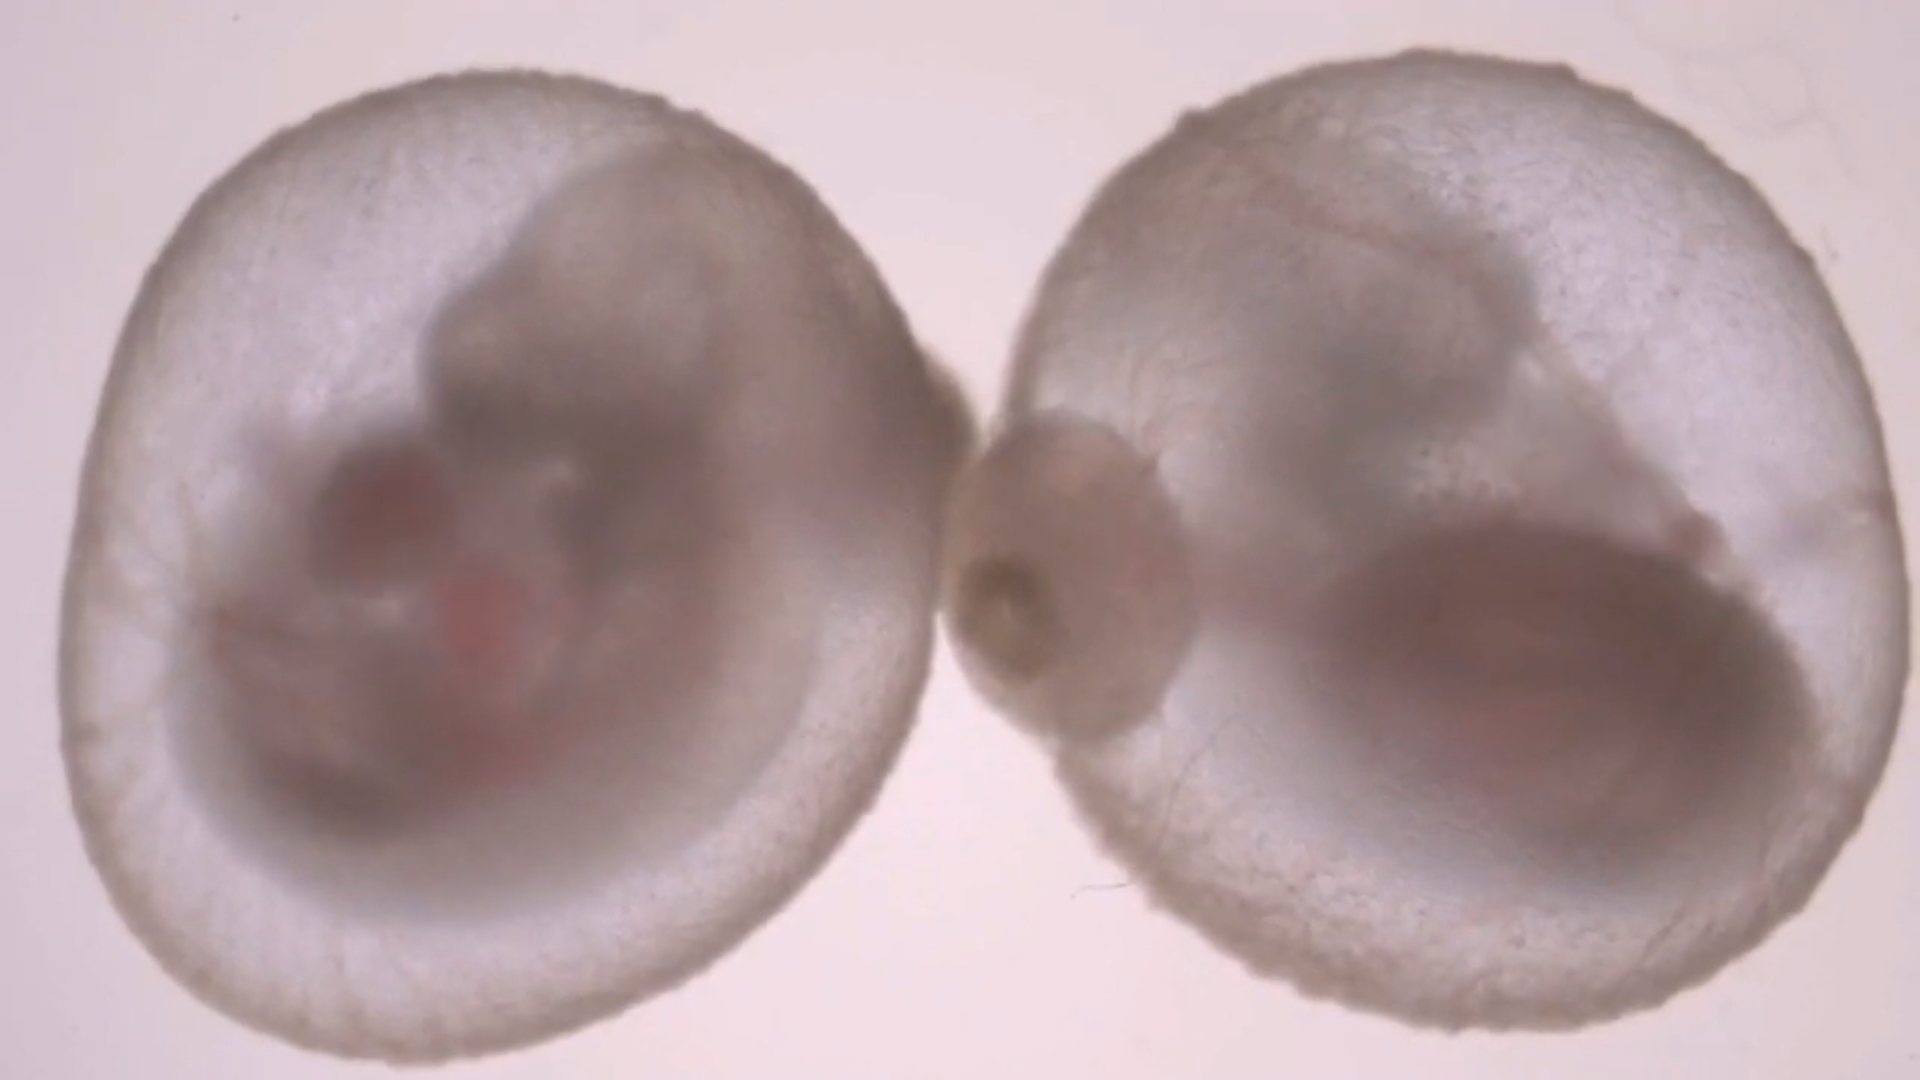

Znanstvenici su prvi put uspjeli uzgojiti zametak sisavca izvan maternice. U studiji objavljenoj u časopisu Nature, tim istraživača s Weizmannovog instituta znanosti u Izraelu kaže da su šest dana uspješno uzgajali više od 1.000 embrija miševa koristeći postupak koji uključuje mehanički uređaj. U prvom dijelu eksperimenta tim je uklonio miševe iz utrobe majki nakon pet dana. Dr. Jacob Hanna, jedan od istraživača na projektu, rekao je da je njegov tim tada uspio uzeti embrij ženki miša nakon oplodnje i uzgajati ga 11 dana u umjetnoj, mehaničkoj maternici. Štoviše, embriji uzgojeni u laboratoriju dosljedno su identični "pravim" embrijima.

Tim je proveo sedam godina praveći stroj koji im je omogućio istraživanje. To je dvodijelni sustav koji se sastoji od inkubatora i ventilacijskog sustava. Svaki od embrija pluta u bočici koja je napunjena posebnom tekućinom prepunom hranjivih sastojaka, kao što možete vidjeti u ovom videu.

Kotač nježno vrti miševe kako se ne bi pričvrstili za zid svog privremenog doma. To sprječava da se embriji deformiraju i nakon toga umru. U međuvremenu, pričvršćeni ventilator pruža miševima kisik, a istovremeno održava protok i pritisak u njihovoj okolini.

U normalnoj trudnoći potrebno je oko 20 dana da se mišji zametak razvije do te mjere da može preživjeti izvan maternice. Do sada su mehanička maternica koju su stvorili dr. Hanna i njegov tim mogli održavati miševe kroz 11 dana rasta. Nakon toga miševi odumiru, jer zametci postaju preveliki da bi preživjeli samo na hranjivim tvarima koje apsorbiraju difuzijom. Potrebna im je opskrba krvlju, a to je sljedeći tehnički izazov koji tim planira riješiti. Jedno potencijalno rješenje uključuje umjetnu opskrbu krvlju koja bi se mogla povezati s posteljicama miševa.